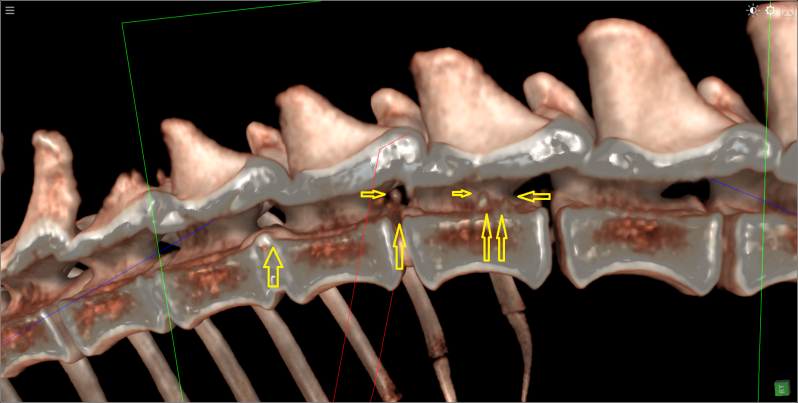

Dalmatier van 11 jaar met verlamming ten gevolge van  discus hernia op de overgang van T13  naar L1.

Eerst beelden van RX,  daarna scan beelden met en zonder contrast , vervolgens 3D beeld.